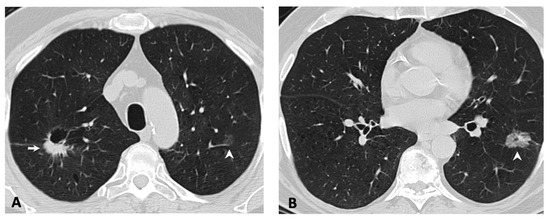

2.2. Imaging Features of the Primary Tumor